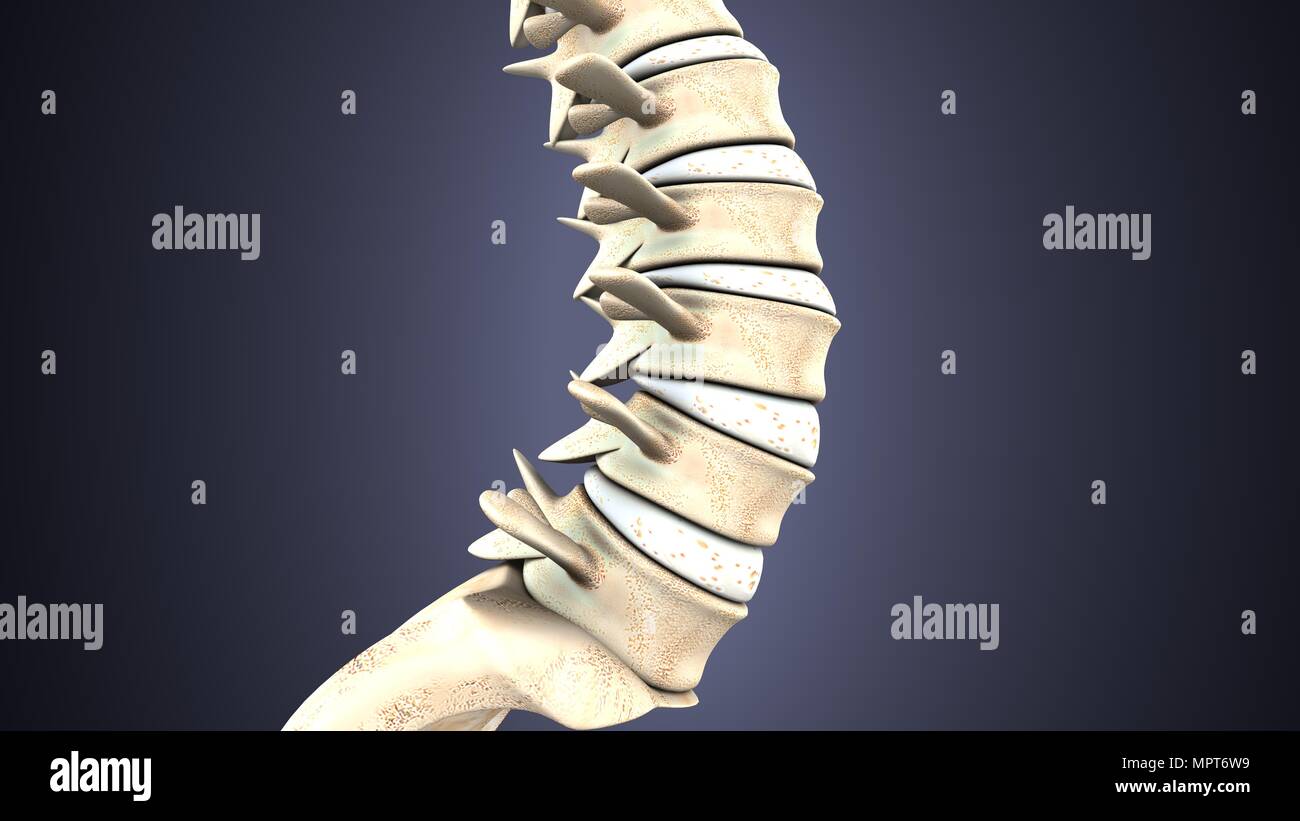

RMKRCW8B–Diagramme de l'os de la jambe droite, montrant l'articulation avec le bassin de la hanche. Date : 1908